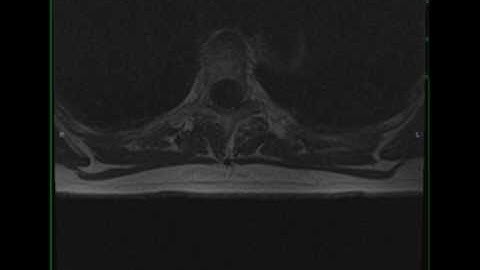

Extradural Schwannoma: 3D Visualization of a Rare Thoracic Spine Tumor and How It Appears on Imaging